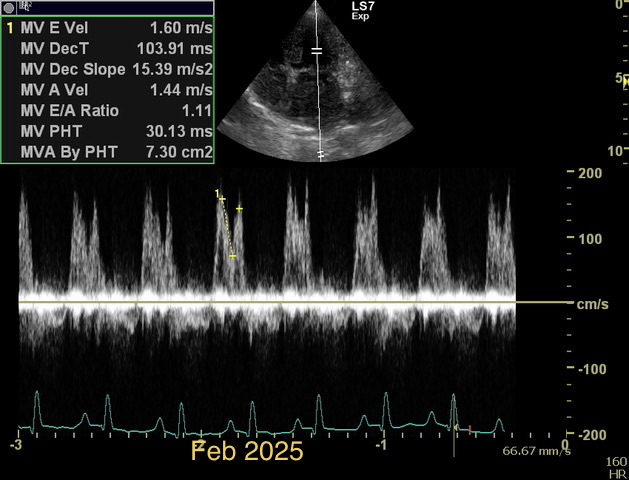

How would you diff b/w reverse remodelling and MV stenosis. Presented at recheck with mod severe pulmonary HT. Smll dog treated for chronic MVD stage C. US= LV under loading, FS > 50%, LAE remains significant. M e-vel is consistently 1.5m/s or higher but dec. time and press half time appear normal. E:A ratio around 1. Would LAE remain with aggressive medical Tx for MVD due to LA remodelling, LA compliance ,chronicity of MVD and ongoing reg. vol. compared to potential for LV to undergo reverse remodelling with Tx. Is stenosis seen much in min breed old dogs? Ls7 vid=2024. Tks!!

I see MS at all ages, because it is frequently missed in young dogs. But this case is not a MS. It is diagnosed as a combination of 2D-echo findings and the typical Minflow profile (E-wave very high frequently >2 m/s) confluent with A-wave. See image and video.